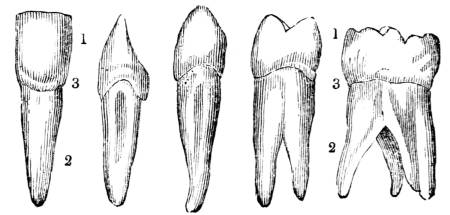

Fig. CXXXVIII.—

View of the Bronchial Tubes terminating

in Air vesicles.

Fig. 138.Fig. 139.

External view.—1. Bronchial tube. 2. Air vesicles. Fig.

139. The same laid open.

is evolved into the surrounding atmosphere.

324. This operation, which is strictly analogous